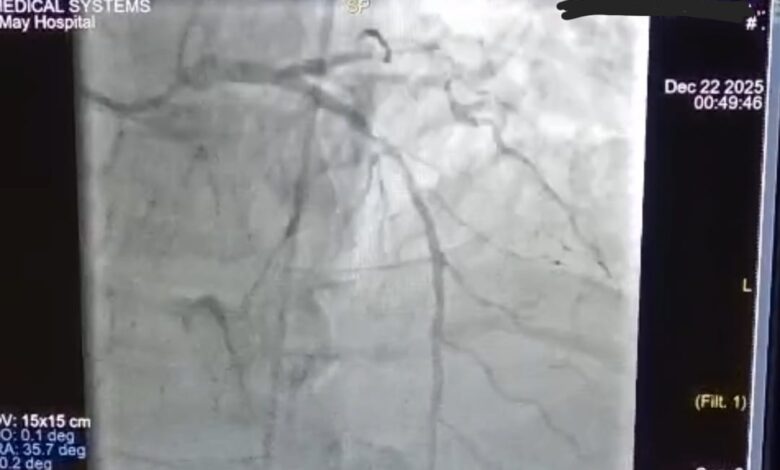

تم على الفور بقسم الطواريء بدأ الانعاش القلبي الرئوي وتركيب انبوبة حنجرية حتى تم استعادة النبض وسرعان ما تم تفعيل بروتوكول القسطرة القلبية الطارئة وتم نقل المريض إلى وحدة القسطرة القلبية وتم إجراء قسطرة لفتح الشريان الرئيسي وتركيب دعامتين دوائيتين.